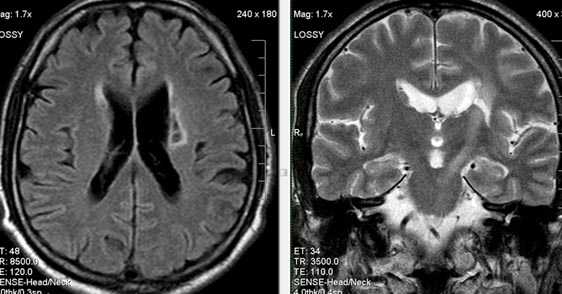

Характерным проявлением ДЭП на МР-томограммах является наличие множественных очагов глиоза.

В белом веществе левой лобной и обеих теменных долей, преимущественно субкортикально, выявлены множественные мелкие очаги хронической ишемии (большинство локализованных в бассейне правой средней мозговой артерии).

Проявлением хронической ишемии является также развитие выраженных дистрофических изменений белого вещества паравентрикулярной локализации - лейкоареоз.

Выраженные дистрофические изменения белого вещества паравентрикулярной локализации - лейкоареоз.